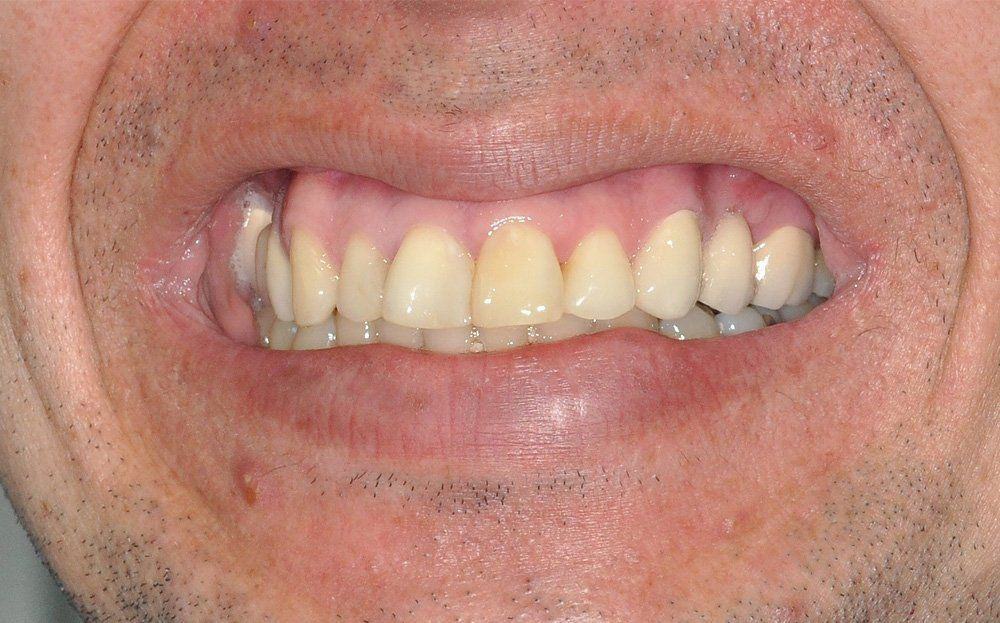

El siguiente caso propone la utilización de prótesis fija de Zirconia y vestibuloplastía como alternativa al tratamiento con implantes e injerto óseo.

El estudio imagenológico evidencia una pérdida ósea severa en altitud y grosor, situación que complejiza la colocación de un implante. Se analizan alternativas de tratamiento y se opta por una vestibuloplastía mediante autoinjerto conectivo de mucosa palatina que se reposiciona sobre la zona del defecto óseo. Además se realiza retratamiento de ambas PFP, ahora en zirconia, por motivos estéticos y oclusales. Se realizan controles posteriores para evaluar la respuesta gingival a la vestibuloplastía.

Conclusiones: La ausencia de un diente no siempre es indicativo de implante. El tratamiento elegido debe tener las menores complicaciones, el mínimo daño, el máximo beneficio y un costo económico de acuerdo a la realidad del paciente. La PFP de zirconio y la vestibuloplastía son alternativas de tratamiento efectivas para la resolución de defectos óseos por ausencia dentaria en la cavidad oral.